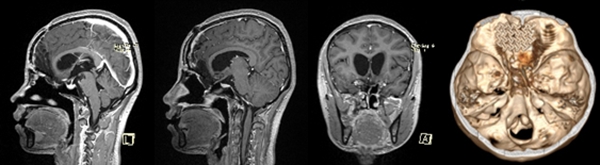

小于術(shù)前的磁共振,能夠清晰看到巨大的腫瘤,像豎起的“啞鈴”一樣,連通顱內(nèi)和鼻腔。重慶醫(yī)科大學(xué)附屬第二醫(yī)院供圖

神經(jīng)外科主任謝宗義接診后,立即意識(shí)到該腫瘤的復(fù)雜性和危險(xiǎn)性:它像一個(gè)巨大的“啞鈴”,一個(gè)頭長(zhǎng)在顱內(nèi),嚴(yán)重壓迫腦組織;另一個(gè)頭掛在鼻腔,幾乎把鼻腔填滿;中間的連桿則破壞顱底,把顱底骨頭侵蝕出一個(gè)大洞,牢牢卡在里面。仔細(xì)詢問(wèn)后,謝宗義得知小于已經(jīng)出現(xiàn)了頭痛、厭食、視力下降等顱內(nèi)高壓的危險(xiǎn)信號(hào),病情兇險(xiǎn)。